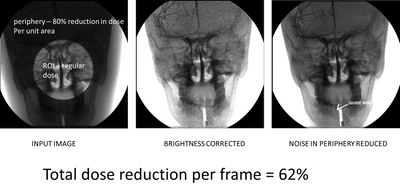

As image guided interventional procedures continue to replace invasive surgical procedures and longer patient x-ray exposure times are required, there is an urgent need to reduce patient dose without jeopardizing outcomes. We have pioneered ROI techniques to achieve this goal by preserving the best image within the ROI while reducing dose peripheral to the ROI. With recent digital imaging developments we have been able to further improve real-time ROI imaging using differential temporal filtering to reduce noise especially outside the ROI and we have even combined ROI dose reduction and high resolution MAF imaging for biplane image guidance.